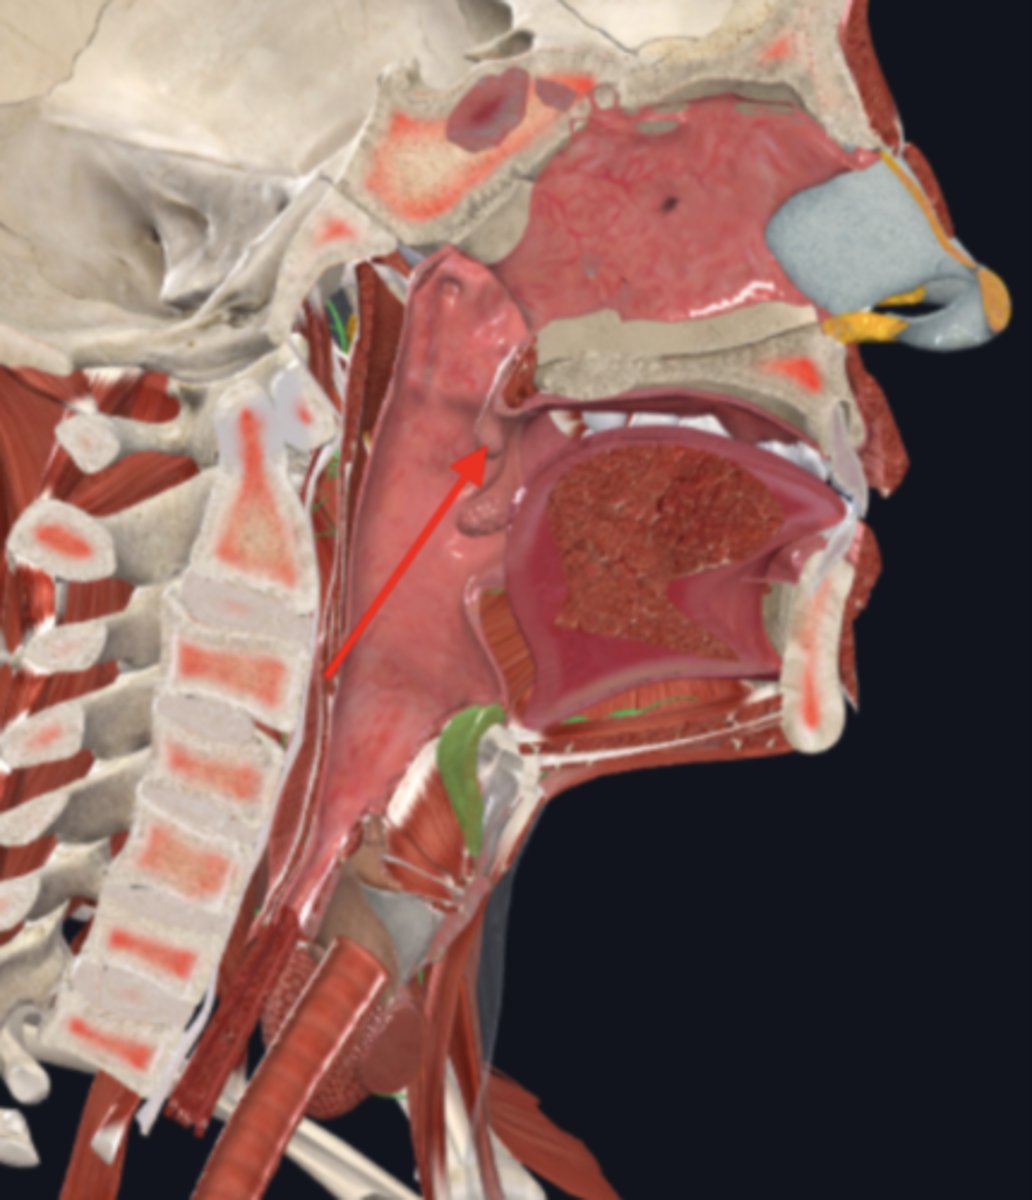

nasopharynx

name the circled region

oropharynx

name the circled region

laryngopharynx

name the circled region